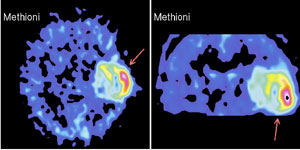

Именно наличие клиники во многом определяет возможности фундаментальных и прикладных исследований ИМЧ. Поэтому прежде всего несколько слов о ней. У нас прекрасные высококвалифицированные доктора и медсестры. Без этого нельзя: ведь мы на переднем крае, и нужна высочайшая квалификация, чтобы выполнять нерутинное, новое. У нас выполняются практически все стандартные манипуляции и наряду с ними и хирургическое лечение эпилепсии и паркинсонизма, проводятся психохирургические операции, в том числе и хирургическое лечение обусловленного героином обсессивно-компульсивного синдрома, знаменитая «пересадка мозга», точнее имплантация фетальной мозговой ткани, лечение магнитости-муляцией мозга, лечение афазии с помощью электростимуляции и многое другое. Накоплен десятилетний опыт клинических обследований с помощью позитронно-эмиссионной томографии. На рисунках приведена малая толика того, что может диагносцировать этот метод томографии. У нас лежат тяжелые больные, и мы стараемся помочь с помощью вышеперечисленных методов даже тогда, когда все остальные попытки были неудачны. Конечно, это удается не всегда. Но безграничных гарантий в лечении людей дать невозможно, а если кто-то дает их, это всегда вызывает очень серьезные сомнения.

Вообще, благодаря технике позитронно-эмиссионнной томографии (или сокращенно ПЭТ), стало возможно детальное изучение одновремено всех областей мозга, отвечающих за сложные “человеческие” функции мозга. Суть метода состоит в том, что малое количество изотопа вводят в вещество, участвующее в химических превращениях внутри клеток мозга, а затем наблюдают, как меняется распределение этого вещества в интересующей нас области мозга. Если к этой области усиливается приток глюкозы с радиоактивной меткой - значит, увеличился обмен веществ, что говорит об усиленной работе нервных клеток на этом участке мозга.

А теперь представьте, что человек выполняет какое-то сложное задание, требующее от него знания правил орфографии или логического мышления. При этом у него наиболее активно работают нервные клетки в области мозга, “ответственной” именно за эти навыки. Усиление работы нервных клеток можно зарегистрировать с помощью ПЭТ косвенно, по увеличению локального кровотока в активированной зоне. (Более ста лет назад было показано, что усиленная работа нервных клеток приводит к увеличению локального мозгового кровотока в этой области.)

Таким образом, удалось определить, какие области мозга “отвечают” за синтаксис, орфографию, смысл речи и за решение других задач. Мы предъявляем испытуемым различным образом организованные задания, при выполнении которых необходимо «задействовать» определенные свойства речи. Например, отдельные слова, предложения, связный текст. Сравнивая ПЭТ изображения, получаемые при этой деятельности, мы можем определить, где в мозге происходит обработка отдельного слова, где синтаксиса, а где смысла текста. Видны зоны, активирующиеся при предъявлении слов, неважно, надо ли было их читать или нет. Зоны, отвечающие за смысл текста, и другие. Интересно, и это будет рассмотрено ниже, что удалось обнаружить зоны, активирующиеся, чтобы «ничего не делать».

Можно говорить о двух видах стереотаксиса. Первый, нефункциональный, применяется тогда, когда в глубине мозга имеется какое-то органическое поражение. Например, опухоль. При попытке ее удаления с помощью обычной техники придется проходить через здоровые, выполняющие важные функции структуры, и больному может быть нанесен вред, иногда даже несовместимый с жизнью. Однако эта опухоль хорошо видна с помощью современных средств интровидения: магниторезонансного и позитронно-эмиссионного томографов. Можно рассчитать ее координаты и разрушить ее, или, например (еще один метод, развиваемый в ИМЧ), ввести с помощью малотравматичного тонкого щупа радиоактивные источники, которые выжгут опухоль и за это же время распадутся. Повреждения при проходе сквозь мозговую ткань минимальны, будет уничтожена только опухоль, причем иногда очень сложной формы, очень агрессивная, и уничтожена радикально. Мы провели ряд таких операций несколько лет назад, и до сих пор живут больные, у которых при традиционных методах лечения не было никакой надежды.